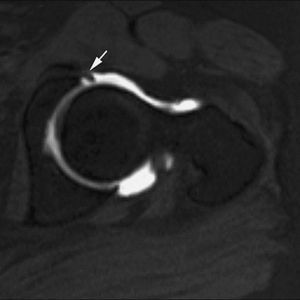

Los cuerpos libres pueden adherirse a la sinovial o bien flotar libremente en el espacio articular. La RM convencional muestra con gran fiabilidad los cuerpos libres en las secuencias T2 si existe derrame articular. La sensibilidad y especificidad de la RMA para detectar cuerpos intraarticulares libres es significativamente superior al distender la articulación y separar los cuerpos libres de la cápsula apareciendo completamente rodeados por el líquido (figs. 13 y 14)4,5,11,12,17. La detección adecuada de estas lesiones es fundamental para plantear la artroscopia terapéutica, evitando el dolor y previniendo el desarrollo de osteoartritis.

Fig. 13.--Voluminosos cuerpos osteocondrales libres en receso capsular anterior del codo. Corte axial de RMA potenciado en T1 con técnica de supresión grasa que demuestra la existencia de dos cuerpos condrales de gran tamaño en la vertiente anterior del codo (flecha).

Fig. 14.--Cuerpo condral libre. Corte en proyección ABER de RMA potenciado en T1 con técnica de supresión grasa que muestra un pequeño cuerpo condral libre en receso capsular posterior del hombro. Nótese la existencia de una lesión de Perthes.